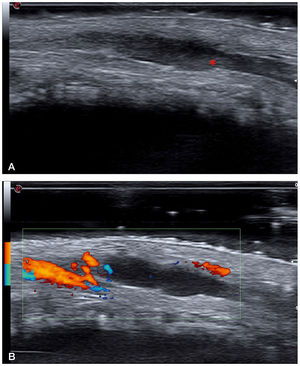

A 54-year-old man, with no relevant past personal history was diagnosed with a stage IIA 2.1mm Breslow thickness melanoma in the medial lumbar region after a regular check-up. Subsequently, a surgical wide excision was performed, followed by an extension study with bilateral inguinal lymph node ultrasound which revealed no pathological findings. Additionally, a right inguinal SLNB performed tested negative. Fifteen days after surgery, he consulted for pain in the dorsal shaft of the penis. Physical examination revealed the presence of an indurated subcutaneous cord with no additional findings (fig. 1). A cutaneous ultrasound (Esaote MyLab Gamma®, linear probe of 6-18 MHz) revealed the presence of a dilated, hypoechoic, non-compressible tubular structure with hyperechoic content and no Doppler flow inside, which was consistent with thrombosis of the penis superficial dorsal vein (fig. 2). A suspected diagnosis of PMD due to inguinal SLNB followed. The patient was assessed by the urology department, which prescribed analgesic treatment with diclofenac and performed a soft tissue ultrasound that eventually confirmed the diagnosis of superficial venous thrombosis without deep involvement. The patient was also evaluated by the hematology department, which ruled out other causes of primary thrombophilia and administered low molecular weight heparin (LMWH). The course of the disease was favorable, and serial ultrasound follow-up confirmed the resolution of thrombosis after 2 months. LMWH was discontinued after resolution, and no recurrences or thrombophlebitis in other areas have been reported at the 18-month follow-up.

a: B-mode ultrasound image (18 MHz) showing a hypoechoic and dilated tubular structure, which is consistent with a superficial vein. This structure was not compressible under pressure. The hyperechoic content indicated by the asterisk corresponds to the intraluminal thrombus. b: Power Doppler ultrasound image showing absence of flow inside the thrombosed vein. The image Doppler flow comes from one of the dorsal arteries of the penis.